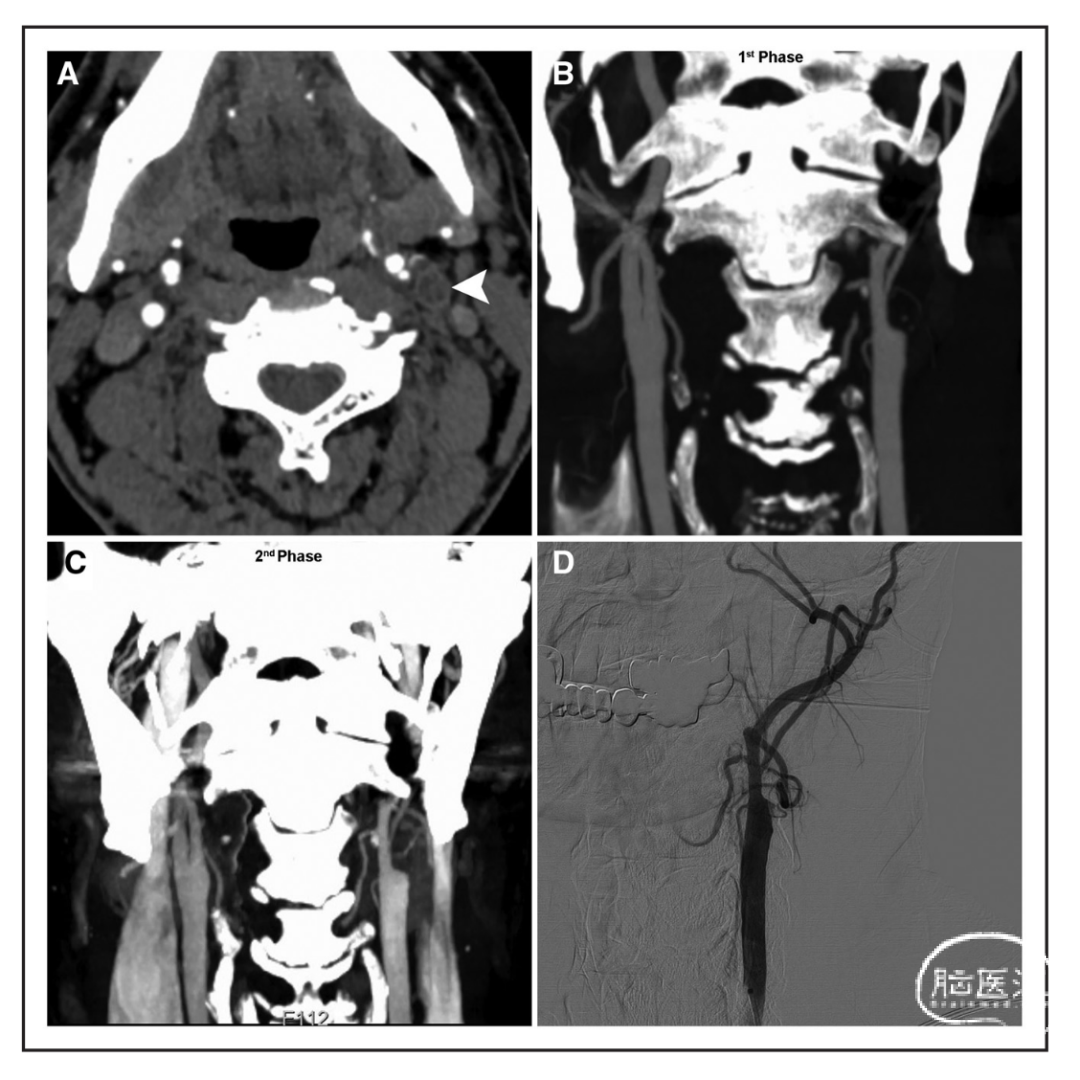

采用数字减影血管造影(DSA)作为诊断近端颈内动脉真性闭塞或假性闭塞的参考标准成像。DSA上显示C1近端ICA闭塞,且无造影剂通过C1至远端或导丝或导管无法通过,称为颈动脉真性闭塞(ICA-TO)。CTA上的C1近端ICA闭塞被定义为动脉期CTA上的颈ICA近端节段完全不显影。ICA-TO被定义为CTA和DSA均显示闭塞。我们将CTA颈动脉环征定义为轴向最大强度投影图像上ICA C1最大狭窄水平下血管壁一半及以上周长的环状外观(图1A)。CTA颈动脉环征可以是增强的或非增强的。我们将延迟造影剂填充现象定义为mCTA的第二时相显示在远端ICA C1段延迟显示动脉造影剂,而不是在mCTA的第一时相。

图1. 一个典型病例,左颈内动脉(ICA)C1段真性闭塞的患者,颈动脉环征呈阳性,延迟造影剂填充呈阴性。在轴向最大强度投影图像(箭头,A)显示颈动脉环征阳性。与多时相CTA的第一时相相比,第二时相(C)没有显示造影剂填充延迟,左侧颈动脉闭塞在CTA早期和晚期(C和D)均位于同一位置,这一点通过数字减影血管造影和血管内操作(D)得到证实。